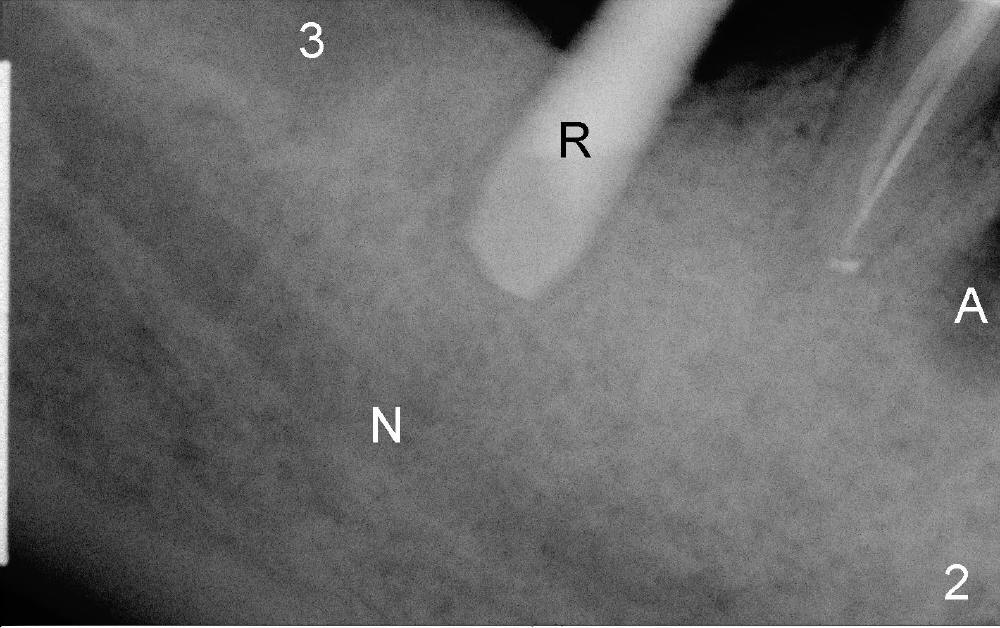

不妨先拍摄X光片看看,三十号牙近中根尖阴影好像没有那么可怕(图二A),但愿它能奇迹般自行愈合,免得造成邻牙植牙失败。三十一号牙钻头(R, reamer, 5 mm diameter, 8 mm deep)离下牙槽神经(N)大约四毫米(图二3是正在愈合第三磨牙拔牙窝),钻头以及植牙还可以往下走两三毫米,最后好像达到目的(图三 I:植牙),但是三十号牙近中病变惨不忍睹(箭头)。植牙后让病人口服Amoxicillin,期望三十号牙近中感染不至于蔓延到弱不禁风的植牙区,有没有感染灶邻近植牙成功病例?